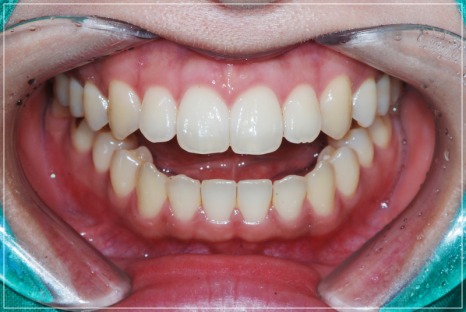

입술이 붕 뜨는 고민을 해결한 모습

위와 같은 상황에서 진행할 수 있는

진료로는 장치를 통한 방법이 있는데

숨겨진 개방교합을 드러내어 턱관절의

상태를 안정시킨 뒤 교정을 진행해주어야

안정적인 해결이 가능하기 때문에

숨겨진 개방교합까지 꼼꼼히 확인하고

그에 맞는 정밀한 진료 계획을

수립할 줄 알아야 합니다.